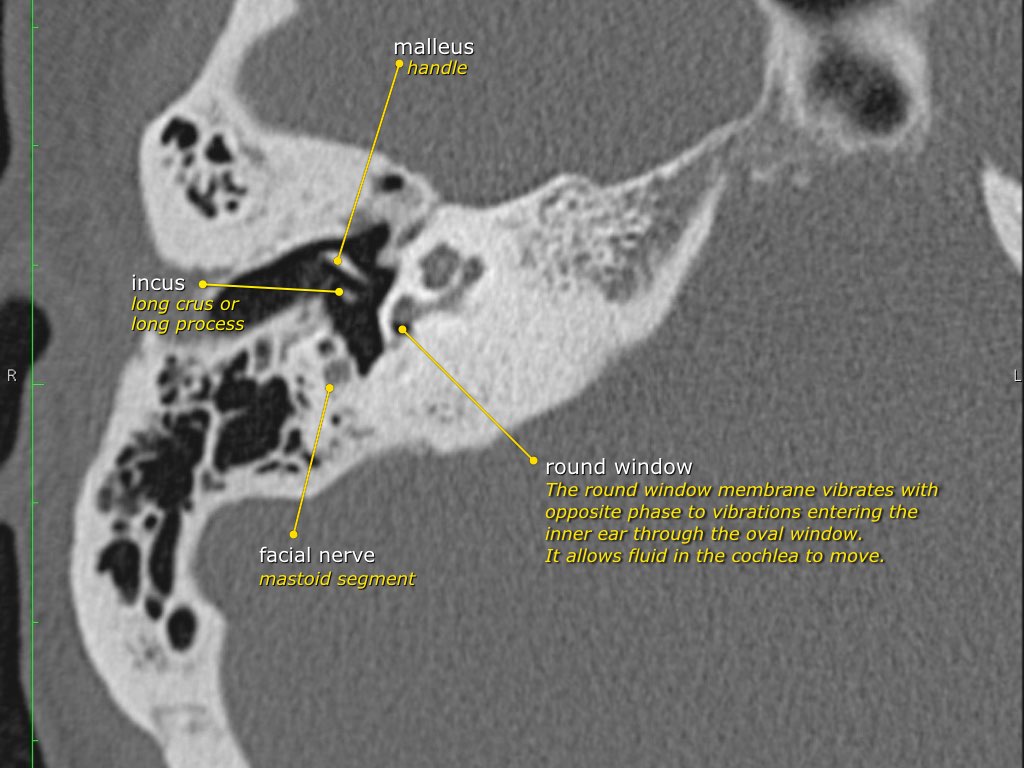

Chuỗi xương con

Trong nhiều hình minh họa, xương đe thường được vẽ kết nối về phía trong với xương búa, tuy nhiên điều này không chính xác.

Trên ảnh tái tạo mặt phẳng coronal bên trái, có thể thấy rõ ràng rằng xương đe nằm ở phía sau ngoài so với đầu xương búa.

Ngành dài của xương đe sau đó chạy xuống dưới và vào trong để tiếp khớp với xương bàn đạp.

Cửa sổ bầu dục và cửa sổ tròn

Đế xương bàn đạp dao động ra vào so với màng tại cửa sổ bầu dục.

Các dao động được truyền từ cửa sổ bầu dục qua nội dịch đến các tế bào lông của cơ quan Corti trong ốc tai.

Cửa sổ tròn có chức năng giải phóng áp lực được tạo ra bởi các dao động dịch lỏng bên trong ốc tai, do đó đóng vai trò như một van giảm áp.